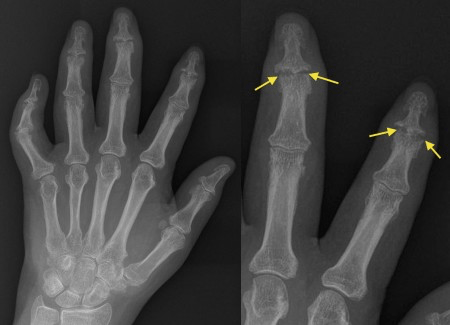

What is the disease associated with the imaging?

OA

Psoriatic arthritis with marginal erosions of the distal interphalangeal joints. The bone gets eroded here first because the overlying cartilage is much thinner than in the centre of the joint. You will notice how the PIP and MCP joints are spared, whereas in the classical appearance of rheumatoid arthritis (RA) we see involvement of the MCP and PIP joints with sparing of the DIP joints.